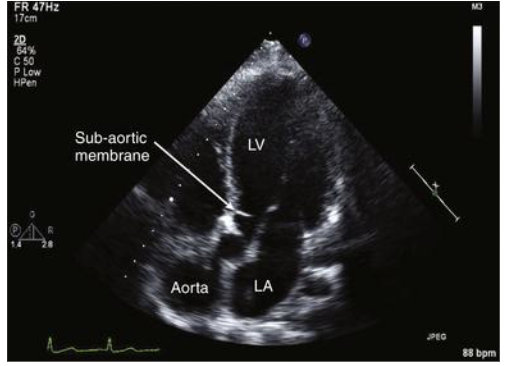

Describe congenital subvalvular stenosis

fibrous membrane or muscular ring in LVOT → obstruction in the outflow

Leads to: narrow LVOT → septal hypertrophy = thicker IVS → dynamic obstruction → mitral valve may get “sucked up”

dynamic because degree of stenosis varies depending on loading conditions